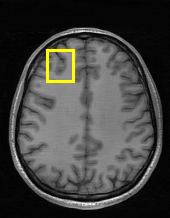

Edge preserving has always been a crucial concern in the design of reconstruction models. To improve the quality of reconstructed images and preserve image edges, some works suggested introducing edge priors in the original restoration problem to preserve image edges [4, 34]. However, they will suffer from complicated algorithm design and time-consuming training processes. Recently, some more efficient methods have been proposed to use edge maps as external guidance for image restoration. For example, Yang et al. [48] used off-the-shelf edge detectors to extract image edges from the degraded images. Fang et al. [12] predicted image edges by constructing an edge reconstruction network. Huang et al. [18] designed a novel dual discriminator GAN framework for solving fast multi-channel MRI, in which one GAN network is built for edge information enhancement. Inspired by these methods, we also consider introducing image edge prior as external guidance to MRI reconstruction since 1) image edges are prominent and distinguishable features in MRI (see Fig. 1), which can serve as a good guide to the model to recover high-frequency details; 2) the ground truth edges can be easily fetched via ordinary edge extraction operators, like Canny, Sobel, and Prewitt, which means that the edge maps can be learned in a data-driven manner. However, how to effectively utilize image edge priors to guide image reconstruction still remains a challenge. In some methods, edge information was simply concatenated with the input image and passed to the next stages. Though this is a simple way to utilize the edge priors, it may not give full play to the guiding role of the edge priors. Therefore, in this work, we want to explore a more efficient and effective mechanism to fully take advantage of image edge priors.

fastMRI is a large-scale MR dataset jointly established by Facebook AI Research and NYU Langone Health. It provides both knee and brain datasets for evaluation. In our work, we use the multi-coil knee dataset, which was acquired on three clinical 3T systems or one clinical 1.5T system using a 15-channel knee coil array. The dataset includes data from two pulse sequences, yielding coronal proton-density weighting with (PDFS) and without (PD) fat suppression. As is shown in Fig. 1, PD images usually contain more structural and prominent edge features than PDFS images, which suggests that it is more challenging to use edge guidance on PDFS datasets. Therefore, we explore the effectiveness of EAMRI on these two modalities. Following [13], for both PD and PDFS knee datasets, we separately filter out 227 volumes (8332 slices) for training and 24 volumes (1665 slices) for testing. The dataset is centrally cropped to .

Moreover, in Fig. 6, we provide a visual comparison of the reconstruction results of these models. We can see that EAMRI has fewer bright spots in the heatmaps, which means less error between the EAMRI reconstructed image and the ground truth image. Meanwhile, according to the zoomed-in images of the selected areas, we can observe that our EAMRI can reconstruct more clean and accurate edges. This further validates the validity of EAMRI. Both the quantitative and the qualitative results for the single-coil MRI reconstruction demonstrate the effectiveness of EAMRI.